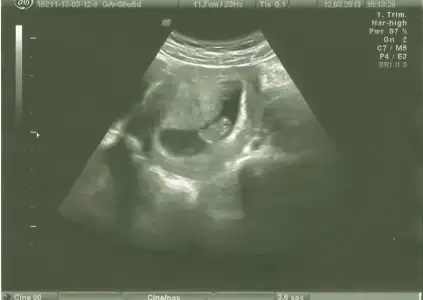

dr soylemeden siz gorun genital nub teorisi ( bebegin cinsiyeti)

bnde yorum bkliyorum kızlarr 2ncisi 11hafta bitiminde 2li tst günüydüü lütfeen

canim bu haftalarda paralel olup erkek cikan cok olduu simdilik paralel seninki 12 13 haftada bu skeil olsaydi kesin kiz derdim ama 11 haftada yorum yapamiyorum

evet bana da paralel geldi.dr da o hafta kıza benziyo dedi .ben 3.kıza hazırlıyorum psikolojimi.bir ihtimal belki rahat bir gebelik olması ve erkek belirtileri vermesi belki erkektir dedirtiyo ama nub ortada.

teoriye göre bakınca paralelse kız dikse erkek diyoruz ama ben bacaktan hiç ayırd edemiyorum bu nubu yahu...